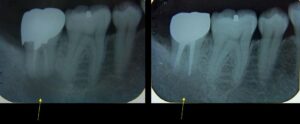

3月9日、10日、今年もこのセミナーが始まりました。私はインストラクターとなっていますが、奥が深い世界で、まだまだ学ぶことの方が教えることより多い感じです。御年83歳になられる阿部先生ですが、例年通り講義、デモを行っています。何十年にも渡って口だけでなく、手で技術を受講生の前で披露するセミナーは他に聞いたことがありません。各ステップがあるので患者さんも毎月決まった時間に来なければなりません。トラブルなく毎年ゴールまで導くさまは年を重ねるごとに、すごいことだなと思います。有歯顎で総合治療を行う際にも咬合をどう仕上げるかは基準がなければ勘だけでやらざるを得なくなります。今年は新受講生が多く、再受講生とあわせて会場がいっぱいでした。再受講生組にはプレゼンさせていただきました。今年も大いに盛り上がり、学べそうです。